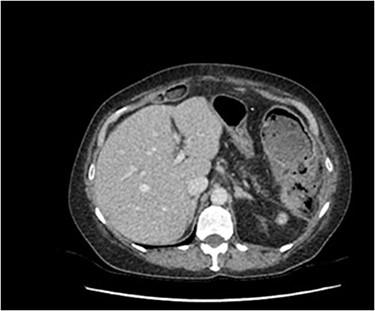

A 70-year-old woman presented to emergency with acute abdominal pain on a background of immunocompromised with type II diabetes and previous splenectomy secondary to trauma in 1980 and multiple previous laparotomies for adhesive bowel obstruction. Computed tomography (CT) abdomen raised the concern of a perforated splenic flexure malignancy (Fig. 1). She had laparotomy that showed grossly dilated large bowel with no obvious perforation; a loop colostomy was formed to decompress the large colon. Intravenous Piperacillin/Tazobactam was the initial antibiotic therapy, with vancomycin and fluconazole later added to cover possible micro-perforation. She was admitted to intensive care unit postoperatively due to ongoing shock and high vasopressor and noradrenaline requirement.

Significant inflammatory change surrounding an irregular appearing splenic flexure with the impression of a likely contained perforation in this region.